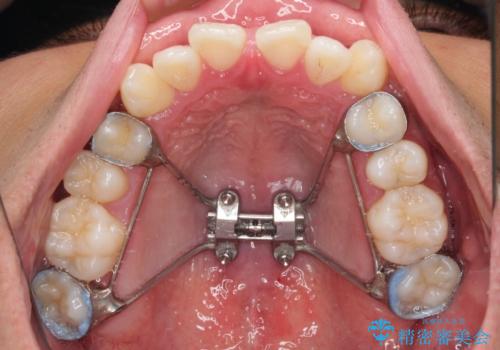

急速拡大装置 歯列弓を拡大して非抜歯ワイヤー矯正

- 上下前歯部のデコボコを主訴として来院された患者様です。

上顎の歯列弓が下顎に対して狭いため、臼歯のかみ合わせがが咬頭対咬頭の状態です。

上顎の急速拡大装置を使用して、上顎骨を側方に拡大することで上顎歯列弓を拡大し、それに伴い下顎歯列弓も拡大できるようにして、歯列を整えていくこととしました。

歯列弓の拡大により約1年で矯正治療を終えることができました。

正中も合わせることができ、非常にきれいに仕上がりました。